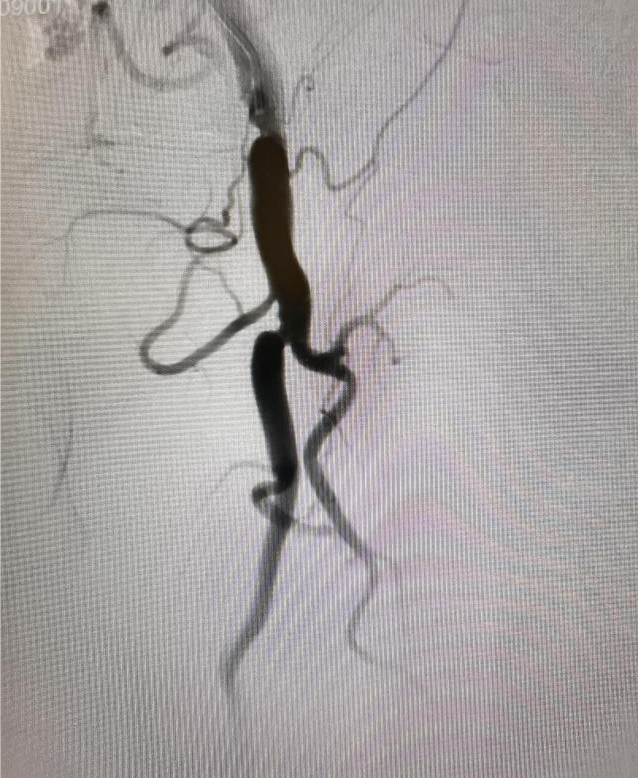

(图4:闭塞导管开通成功,血流恢复)

面对这一技术挑战,刘超医生提出创新性解决方案:“正向不通,就尝试逆向突破。”在充分术前准备和严密风险评估基础上,手术团队果断采用逆行介入技术:于患者膝关节上方约2厘米处对股浅动脉远端进行精准穿刺,同步从近端与远端双向推进导丝。术中巧妙运用超滑导丝配合强支撑导管,实施“双向穿针引线”策略,最终成功实现导丝在闭塞段内的精准“会师”,逐步打通顽固性阻塞,恢复下肢动脉血流。术后患者下肢灌注明显改善,双下肢无力症状显著缓解,恢复情况良好,目前已可逐步开展康复训练。

此次手术的成功,不仅彰显了我院在复杂外周血管介入治疗领域的技术实力,也体现了多学科协作(MDT)模式在疑难重症救治中的关键作用,为类似复杂下肢动脉闭塞性疾病患者提供了新的治疗路径与希望。